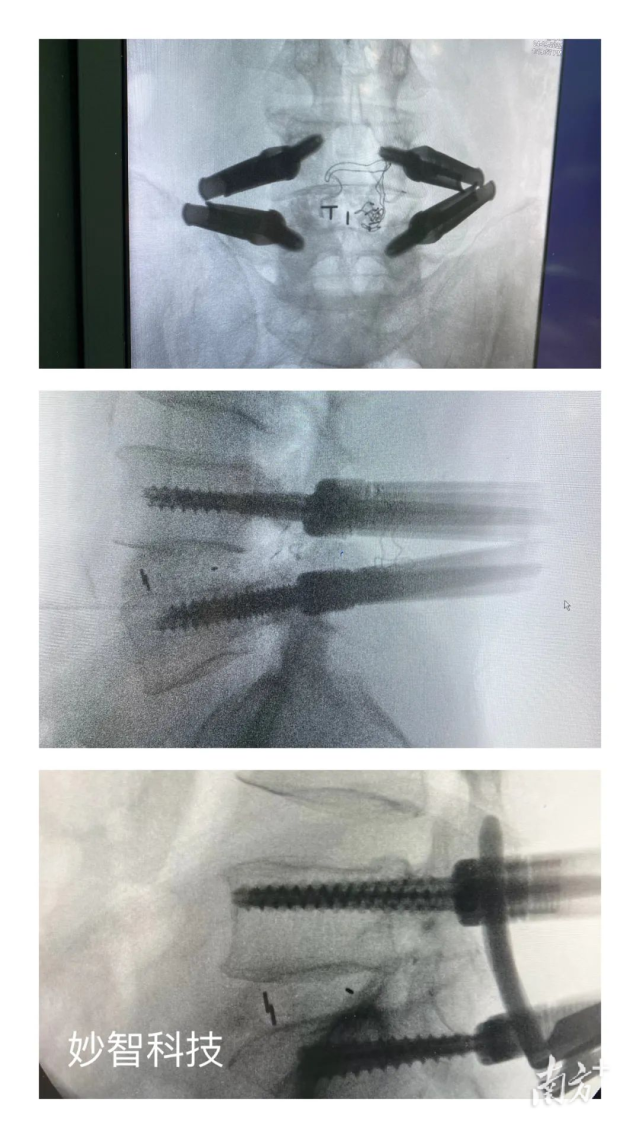

妙智科技研發(fā)的骨科機(jī)器人在臨床中試驗(yàn)

由於新型醫(yī)療器械壹般研究周期較長(zhǎng),目前,妙智科技研發(fā)的骨科機(jī)器人仍在臨床試驗(yàn)階段。截至2022年底,妙智科技已經(jīng)完成了近50例臨床病例,預(yù)計(jì)今年計(jì)劃將完成取證並開(kāi)始售賣(mài)。